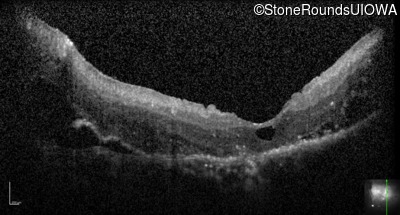

Optical Coherence Tomography - Left - Hand Motion

Exemplar / OCT Stack